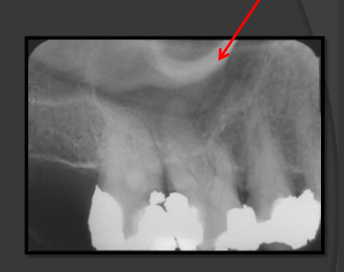

How does the maxillary sinus present in a radiograph?

It is a radiolucent space that sits above the maxillary teeth.

Pneumatization

A name for when the sinus recedes into the bone where a tooth is missing.